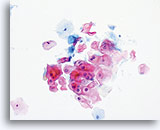

The ThinPrep Pap Test® minimizes the troublesome artifacts inherent in smear and spray fixation. This allows for

the nucleus to be adequately visualized facilitating a more definitive diagnosis. The epithelial cells that are generally incorporated in the ASC category are the mature squamous and squamous metaplastic cells exhibiting changes that are minimal and fall short of a diagnosis of LSIL or HSIL. The nuclei are slightly enlarged and this enlargement is compared to the normal entity of the same cell type. The nuclei may show slight nuclear membrane irregularities but are more often smooth. When dealing with the metaplastic component, one needs to make sure that the irregularities aren’t due to a vacuole(s) pushing the nucleus into the aberrant shape. The chromatin pattern is finely granular and evenly distributed. Chromocenters or nucleoli are generally inconspicuous or absent unless a reactive process is occurring in conjunction with the atypia at which point the differential diagnosis of reactive needs to be considered depending upon the presence or lack of the other criteria.

With either conventional or ThinPrep® slides, an ASC interpretation may arise from any of several different cellular changes, including but not limited to, squamous atypia, atypical squamous metaplasia, and atypical parakeratosis. The criteria for ASC on the ThinPrep Pap Test are as follows:

The images that follow are ThinPrep® Pap Test specimens that reasonably could be interpreted as reactive changes,

ASC-US, and LSIL.